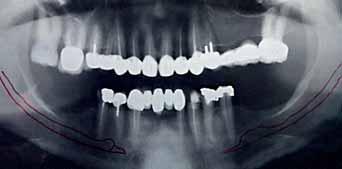

A 60 years old healthy female came into the clinic asking for a

fixed dental appliance to restore the bilateral edentulous posterior spaces of her own (Kennedy class 1).

There was a missing 6 and 7 on each side with compromised 4 and 5 on each.

The volume of available bone was insufficient to place a root form implant on the site of 7 (C-h available bone) a ridge mapping technique was used and a (C-w available bone) was also encountered.

The use of short implant in this case was not a treatment of choice; the crown - implant ratio is > 1.

A unilateral subperiosteal implant was suggested.

The implant design in this case composed of one abutment connected to the peripheral struts by 4 abutment struts for each implant. One hole was drilled on each implant on a peripheral strut (distal aspect) for the placement of titanium fixation screw. Implants should be thoroughly cleaned and sterilized before placement.

After the implant is placed on the ridge a titanium screw is used to fix the implant on the ridge to obtain the primary stability this screw would be of no use after the healing of tissues because the implant would be stable on place by the attachment of the soft tissues to the bone which holds the struts of the implant in between.

After 2 weeks of implant placement the patient came back. A preparation was done to the premolars at both sides and the impression was taken.

4 units bridge was fabricated for each side splinting the implant abutment to the 2 natural teeth of each side.